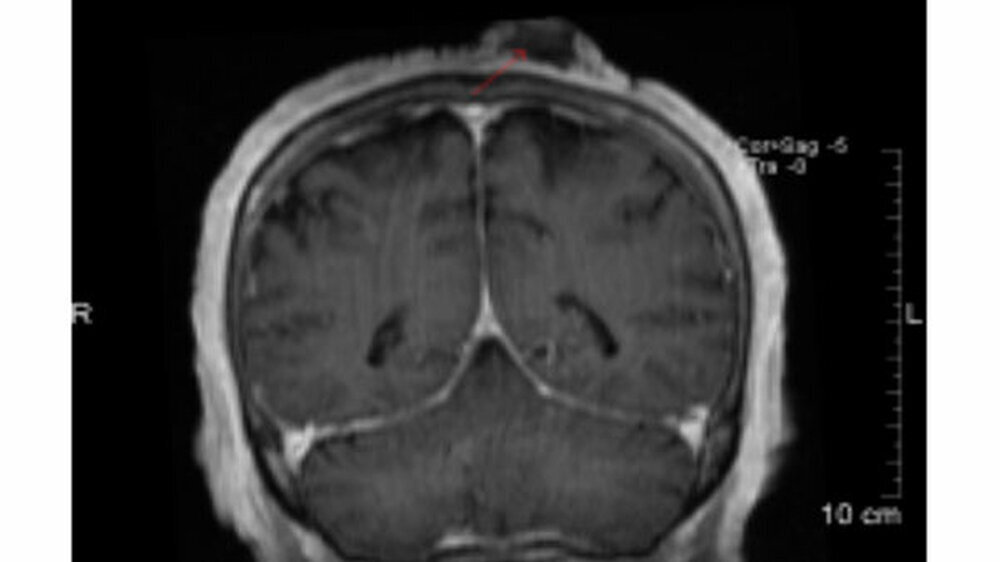

Im MRT zeigte sich eine occipital gelegene, ausgedehnte Raumforderung (Abbildung 4), welche im PET-CT zum komplementierendes Staging mit einem Standard FDG-Uptake (SUV

max

) von 19.4 bestätigt wurde. Es ergaben sich keinerlei Hinweise für eine lokoregionäre Metastasierung, Fernmetastasen oder einen Zweittumor (Abbildung 5).